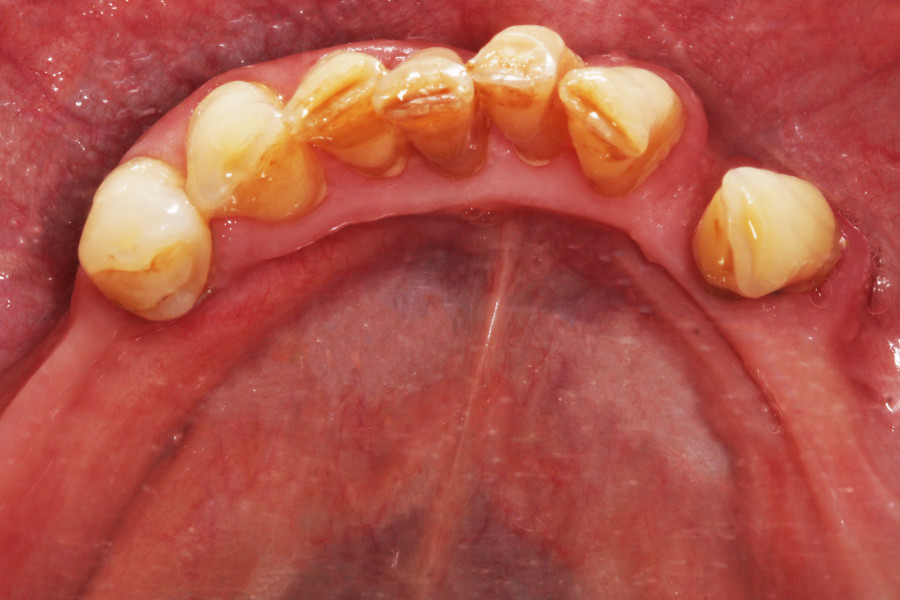

Pacjentka lat 65, zgłosiła się do stomatologa na konsultację, ponieważ niepokoiła ją ruchomości zębów. W pierwszej kolejności została skierowana na wizyt higienizacyjną. Bezzębie w łuku górnym zaopatrzone było całkowitą akrylową protezą, w łuku dolnym pacjentka nie użytkowała żadnego uzupełnienia. Pacjentka niepaląca.

Postępowanie rozdzielono na dwie wizyty. Badaniem klinicznym, oceniając wskaźniki periodontologiczne, uzyskano wartości API 100%, PBI 100% świadczące o konieczności poprawy higieny i procesie zapalnym dziąseł, duże złogi kamienia nad i poddziąsłowego, bardzo obfity biofilm, pogłębione wszystkie kieszonki dziąsłowe, ciężkie zapalenie dziąseł, ruchomości zębów dolnych III stopnia, duży zanik kości. Badanie kliniczne błony śluzowej jamy ustnej nie wykazało zmian patologicznych.

Na drugiej wizycie przeprowadzono dokładną kontrolę pozabiegową. Oznaczono ponownie wszystkie wskaźniki notując znaczną poprawę – API 17%, PBI 33%, sprawdzono głębokość kieszonek i ruchomości zębów.